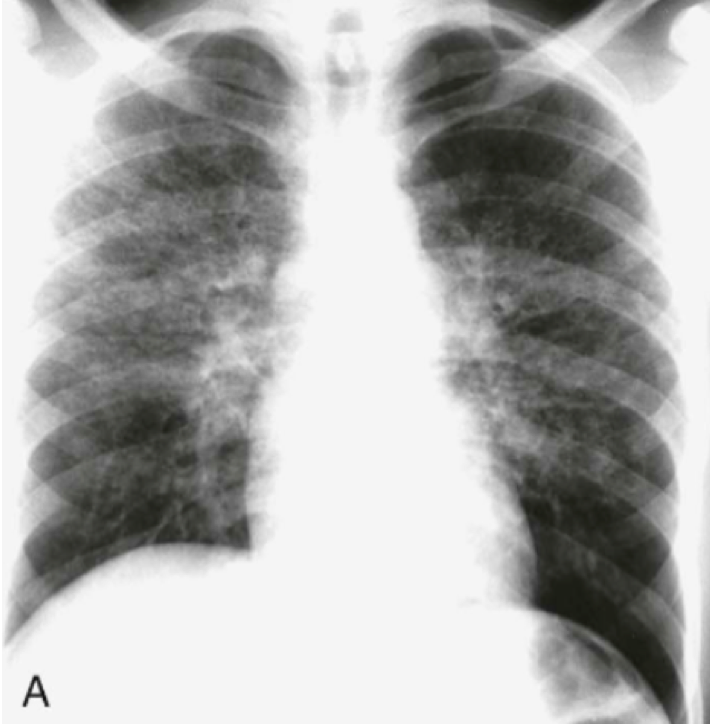

In what disease will you see this in?

Answer

• Multiple Myeloma

• Paget's Disease